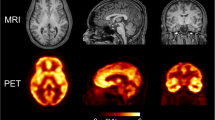

At the voxel level, Logan, MA1, and SA generated parametric images of good quality that represented OGA density in the brain (Fig. 1). The parametric images generated by IRF120voxel were noisier, although the overall image quality was acceptable for quantification. Whole-brain VT values obtained with Loganvoxel, MA1voxel, SAvoxel, and IRF120 were strongly correlated with VT obtained with 2TCM (r > 0.95, P < 0.001 for all; Table 1). Loganvoxel and MA1voxel showed a small bias in VT with 2TCM: − 7.3% (95% CI − 9.2 to − 5.5%; range − 5.6 to − 20.4%) for Loganvoxel and − 2.4% (95% CI − 3.6 to − 1.2%; range − 7.3% to 1.6%) for MA1voxel (Table 2). SAvoxel overestimated VT with a bias of 15.5% (95% CI, 14.6 to 16.4%; range 9.3 to 17.3%). The repeated measures ANOVA was significant (F(3, 36) = 3.206, P = 0.034) and Fisher’s LSD test showed that SA differed from both Logan and MA1. Indeed, SA tended to overestimate VT, whereas graphical analyses underestimate VT compared to compartmental modeling.

The trans-axial parametric images generated by different kinetic models in a single healthy volunteer. Total distribution volume (VT, mL∙cm−3) was obtained with Logan (VTLogan), multilinear analysis-1 (VTMA1), and standard spectral analysis (VTSA). Impulse response function was calculated at 120 min (IRF120)